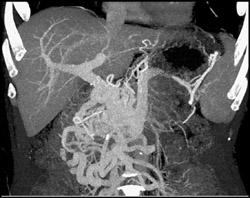

Diagnosis

Decreased Function Left Kidney